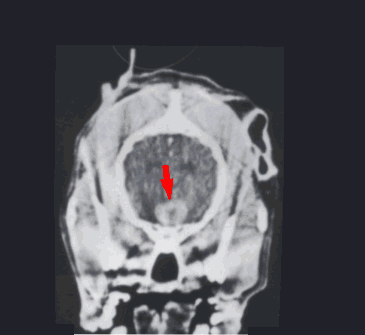

Special imaging of the brain is required to confirm the presence of a pituitary macrotumor and this means either CT (CAT SCAN) or MRI (Magnetic Resonance Imaging). These procedures are expensive; for example, in Los Angeles brain imaging can easily cost a couple of thousand dollars. Special facilities are needed for the equipment involved thus referral to a specialty hospital is usually required. MRI is felt to be superior for imaging the pituitary gland and is the preferred imaging method for this situation; however, CT is more readily available.

Pituitary Macroadenoma